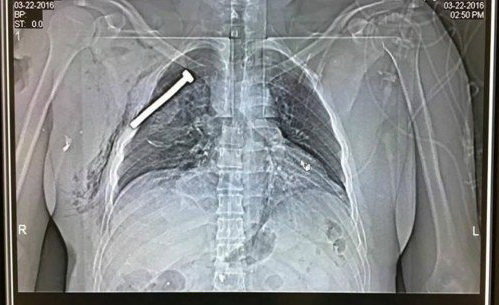

IS 테러범들의 잔혹성을 보여주는 폭탄테러 피해자의 엑스레이 사진이 공개돼 충격을 주고 있다.

미국 현지언론들이 공개한 사진을 보면 브뤼셀 북부에 있는 한 군사병원에서 촬영한 것으로 피해자의 가슴에 박힌 약 8cm의 대못이 선명하게 보인다.

테러범이 폭탄의 살상력을 높이기 위해 폭탄에 내장시킨 파편이라고 한다.

여기서 부상자로 보이는 환자의 엑스레이를 찍은 결과 몸 속에 못이 박힌 것을 확인했다.

엑스레이로 찍은 부상자도 심장에서 얼마 떨어지지 않아 생명에 지장은 없지만 큰일날 뻔한 경우였다.